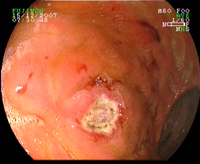

Cancer hémorragique de l'oesophage